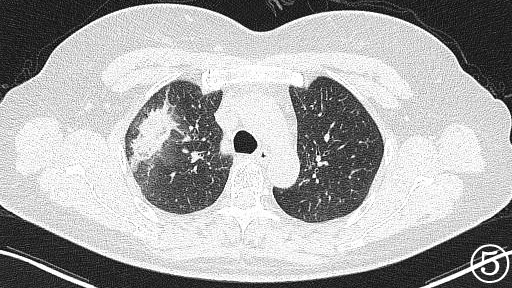

术前进行常规CT扫描确定消融区域及穿刺路径,局部麻醉后利用微波消融针,从体表定位点沿着穿刺路径逐层穿刺到达预定消融区域(图②),予以单次多点消融靶区,最后可见消融后靶区完全覆盖病变区域(图③、④)。手术过程仅耗时约1h,术中肺尖可见少量出血,未发现气胸及咯血等并发症,术后3天复查影像可见消融区完全覆盖病灶(图⑤),病人安然出院,从而达到治愈性消融的目的。